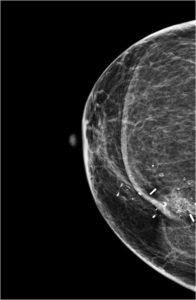

43 year female patient has come for routine screening mammogram...

Read More